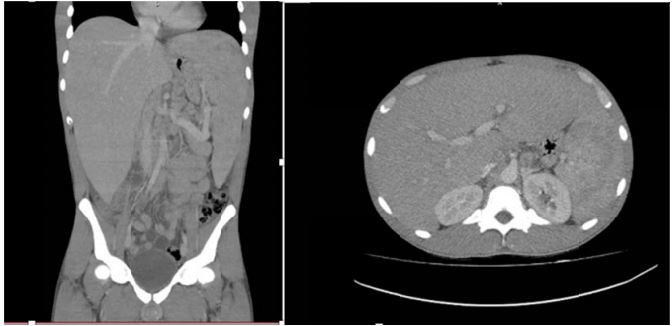

Mulher, 23 anos, procura atendimento referindo febre diária, astenia e perda de 8kg em um mês, além de aumento do volume abdominal com empachamento pós-prandial. Exame físico: Regular estado geral, emagrecida descorada (+2/4); micropoliadenopatia cervical bilateral. Abdômen: fígado palpável a 8cm do RCD, baço a 8cm RCE, doloroso à palpação. Exames laboratoriais: hemoglobina 8,7g/dL; leucócitos 43.320/mm³ (60% eosinófilos), plaquetas 98.00/mm³. Tomografia computadorizada de abdômen: imagem abaixo.

Realizada punção esplênica: presença de estruturas com parede dupla birrefringente e brotamentos.

Considerando a principal hipótese diagnóstica, é correto: